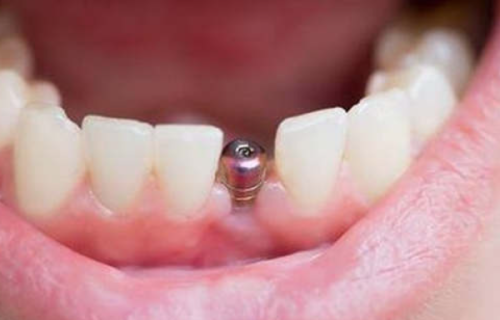

沈阳馨格口腔门诊部有不少特色项目。其中,超声波洗牙是其一大特色。医生洗牙技术娴熟,注重卫生,洗牙过程舒适,没有疼痛感,还会细心为患者讲解科普知识,以及回家后如何正确刷牙等注意事项。另外,种植牙项目也值得一提,该门诊部开设的微创种植牙技术优势明显,单颗缺牙从种牙开始到结束大概需要20分钟即可完成手术,伤口小,术后容易修复,这对医生的种牙技术要求极高。